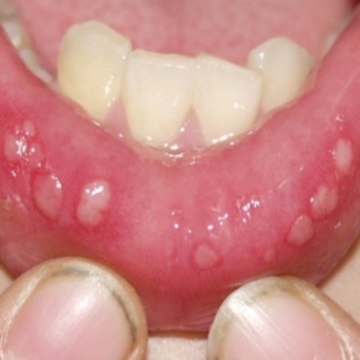

4. 칸디다성 구내염

칸디다균은 우리 입안에 항상 존재하고 있는 균입니다. 그런데 여기에 면역력이 떨어지게 되면 그 여러 증상 중의 하나로 입안이 헐거나 하는 것을 볼 수 있습니다. 즉 면역력이 떨어진 시기에 칸디다균이 이상증식하는 것이 원인입니다.

입 안에 하얀 설태가 끼고 이것을 벗겨내면 피가 나거나 음식을 먹으면 통증을 느끼기도 하고 맛을 못 느끼기도 합니다.